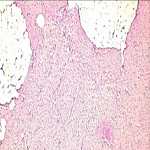

Prevalence, predictors and etiologies of NRD: out of the 703 newborns, 334 had NRD, giving a prevalence of 47.5%. Newborns with NRD and those without NRD had similar mean birth weight (2759±954 vs. 2845±748 respectively), mean maternal age (30.3±5.3 vs. 30.3±5.0 respectively) and maternal parity (1.3±1.8 vs. 1.2±1.7 respectively). In a multiple logistic regression model, prematurity, male gender, high birth weight (≥ 4000 grams), an APGAR score < 7 at the 1st minute, fetal distress and elective caesarean delivery were independent predictors of NRD (Table 2). Attending four or more antenatal visits, prolonged rupture of membranes above 12 hours and intra-partum maternal fever independently reduced the odds of neonatal respiratory distress. None of the maternal factors (maternal age, marital status and parity) was associated with NRD. The etiologies of NRD in the 334 newborns were dominated by neonatal infections (Figure 1).

Figure 1: etiologies of neonatal respiratory distress